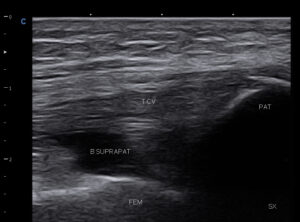

Colectie lichidiana suprapatelar (genunchi)